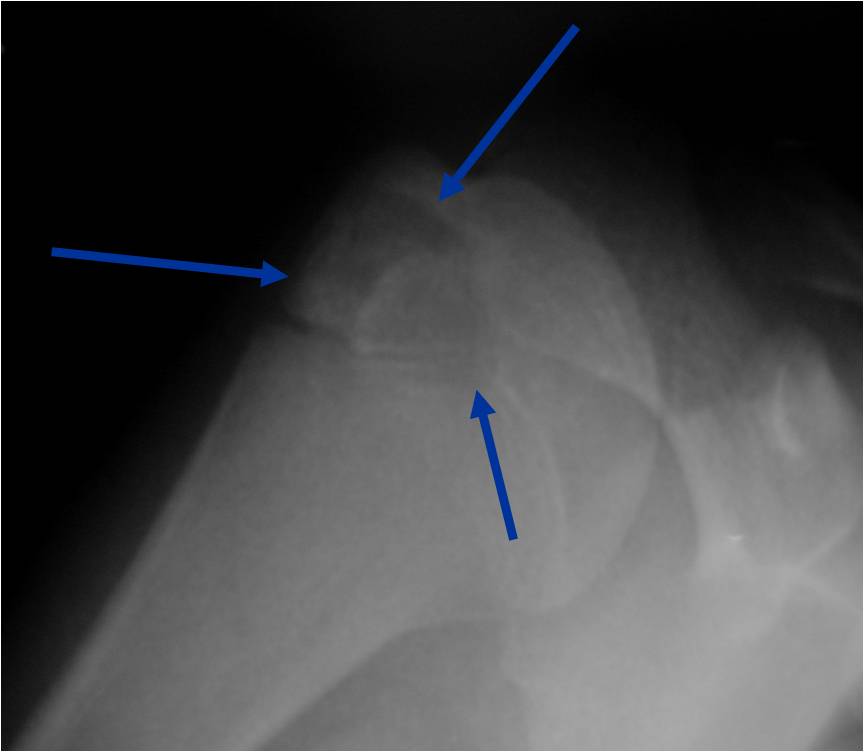

Radiographic Presentation

- Presents as a highly defined/well circumscribed geographic oval/round lytic defect

- Surrounded by rim of sclerotic bone

- Usually in epiphyseal region

- Lesion ranges from 3 cm to 6 cm diameter

- Usually radiolucent

- May have fine trabeculae and irregular calcifications

- Calcifications are often better detected with a CT scan but are not uniformly present

- Lesions may expand the bone and new periosteal bone may form

- Bony end plate, cortex, bone contour are unaffected

- (Plain x-ray appearance)

- Geographic lytic lesion IA/IB margin of sclerosis

- Usually Eccentric more often than Central in the bone

- Rarely expansile (rarely penetrates the cortex)

- Calcified chondroid matrix 30%-50% of cases

- Often better detected with a CT Scan

- Periosteal Reaction 30-50% of cases

- Usually occurs in Adjacent Diaphysis/Metaphysis since epiphysis is intraarticular and not surrounded by periosteum